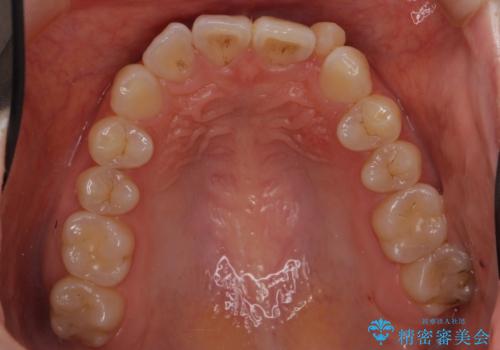

歯を大きくかぶせるスペースを作るため、右上の奥歯を後ろに下げています。

矯正用ミニスクリューを1本、使用しています。

左上の前歯は小さいため、(矮小歯)左右対称になるようにセラミックで形を修正する治療も併用しています。